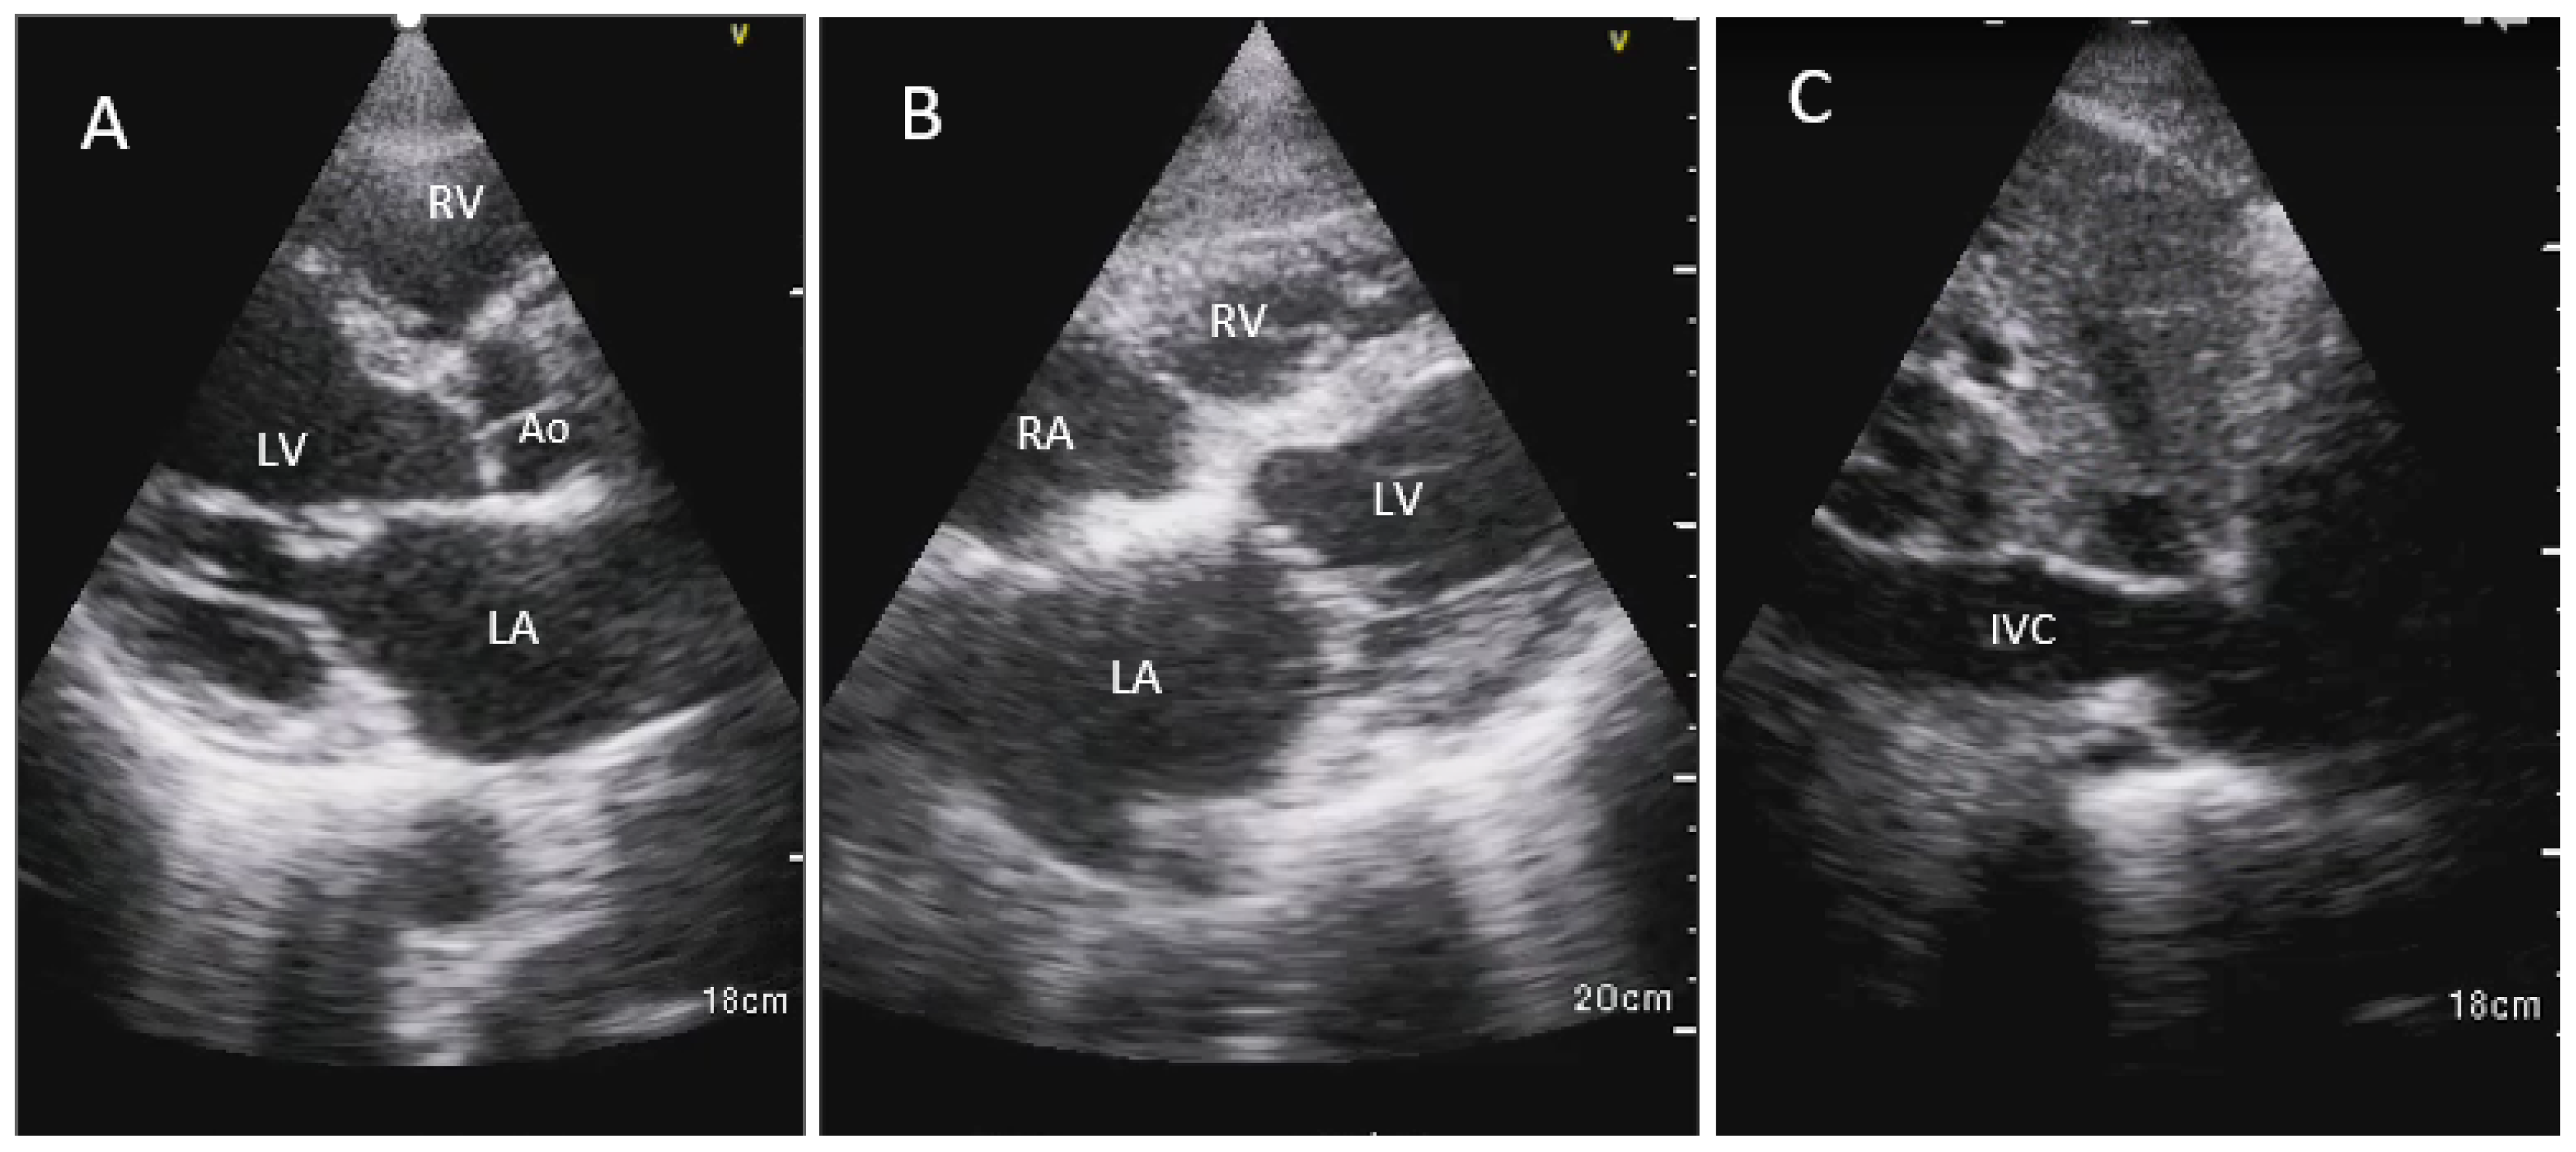

2.1.1. HHE Training for APPs

2.1.3. APPs/Patient Enrollment and HHE Imaging

2.1.4. HHE Imaging Methods